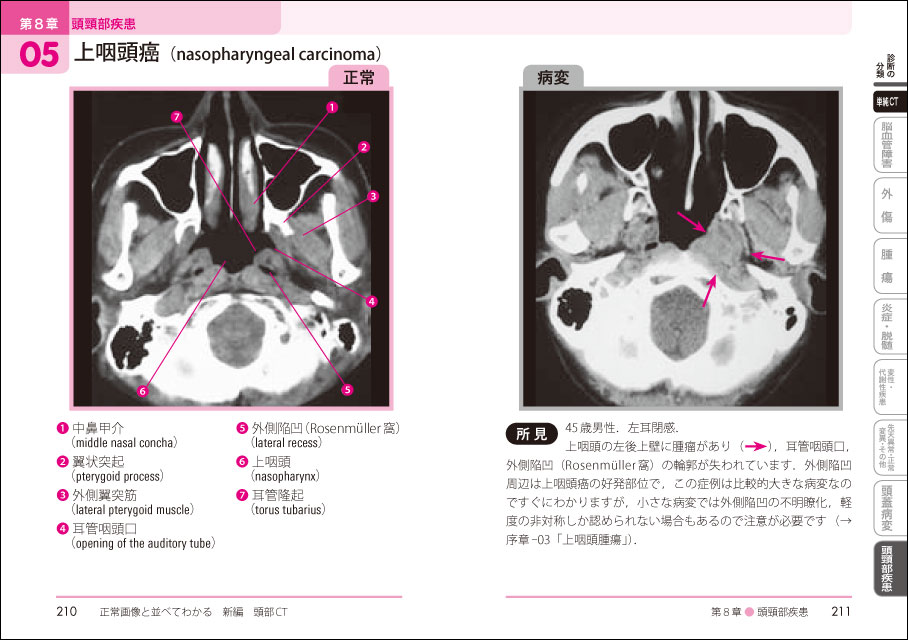

正常画像と並べてわかるシリーズ 正常画像と並べてわかる 新編 頭部ct